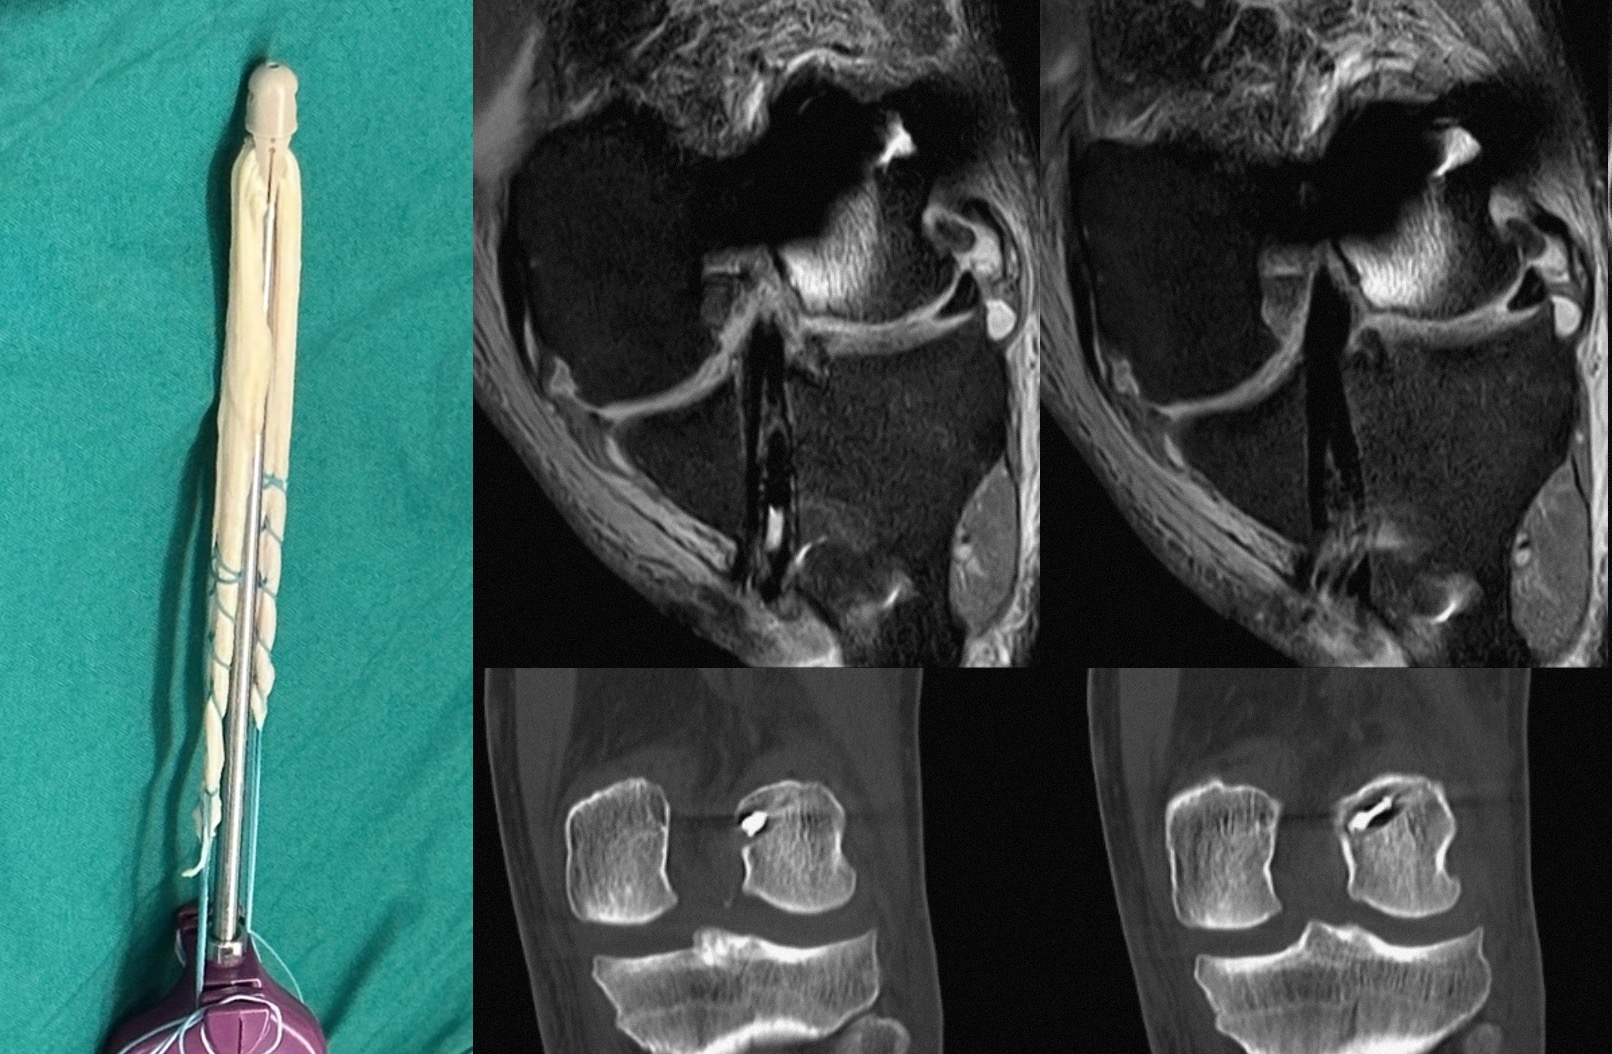

这名接受治疗的患者曾因踢足球而扭伤膝关节,运动时时常出现膝关节疼痛和不稳定感,经检查后诊断为“左膝前交叉韧带断裂”。经骨科主任吴松评估后,考虑到患者具有较高的运动需求,科室讨论决定采用最新引进国内的AperFix韧带固定装置。7月11日上午,在吴松主任及沈民仁副教授指导下,由何金深副研究员主刀,带领王梓力博士及梁驰博士等运动医学团队核心成员成功为其实施了AperFix前交叉韧带重建手术(术后核磁共振及CT影像学如下图所示),这也开创了省内前交叉韧带新型固定方式的先河。

据何金深介绍:AperFix前交叉韧带重建手术是近年国际上开展的一种基于新型固定装置与固定方法的前交叉韧带重建术式,与传统术式相比具有明显优势。首先,相较于传统的固定方式,这种股骨撑开的固定方法有着更高的生物力学性能,即更强的稳定性,因此极少出现肌腱重建后股骨端的蹦极效应与雨刮效应等并发症。其次,该术式下的移植肌腱分成4股折叠在固定装置上,术者可通过调整肌腱植入角度,更精确模拟前交叉韧带的双束解剖结构。此外,该术式胫骨部分中轴挤压固定的特性能够将移植肌腱环形压缩,从而使骨肌腱结合面最大化,最终减少骨腱愈合时间,有利于患者更快地进行康复训练。因此,该新技术的成功开展,标志着膝关节韧带损伤患者今后将可能获得更好的预后。